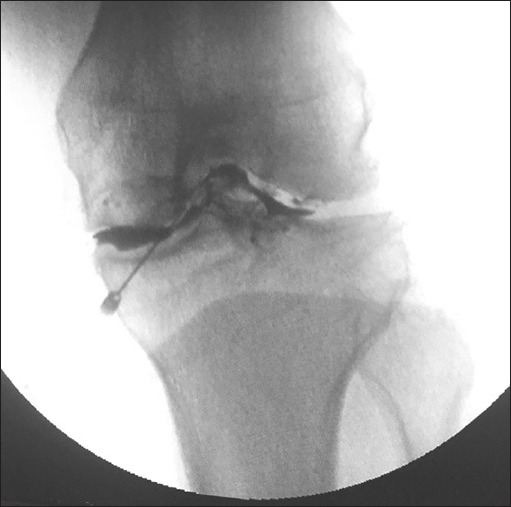

Material and methods: Fifty patients (aged more than 50 years) with pain pattern consistent with osteoarthritis of the knee who did not respond to conservative treatment were included in the study. They were randomly divided into two groups of 25 each: group I (n = 25) patients were administered fluoroscope-guided intra-articular knee injection of bupivacaine and steroid, and group II (n = 25) patients were administered intra-articular knee injection of PRP. In group I, patients were administered 9 ml of drug solution comprising 8 ml of 0.5% bupivacaine and 1 ml of triamcinolone (40 mg). In group II, patients were administered 6 ml of PRP. Pain, patient satisfaction, and the Western Ontario and McMaster Universities Osteoarthritis Index (WOMAC) were assessed at different time intervals before and after the procedure for up to 12 months.